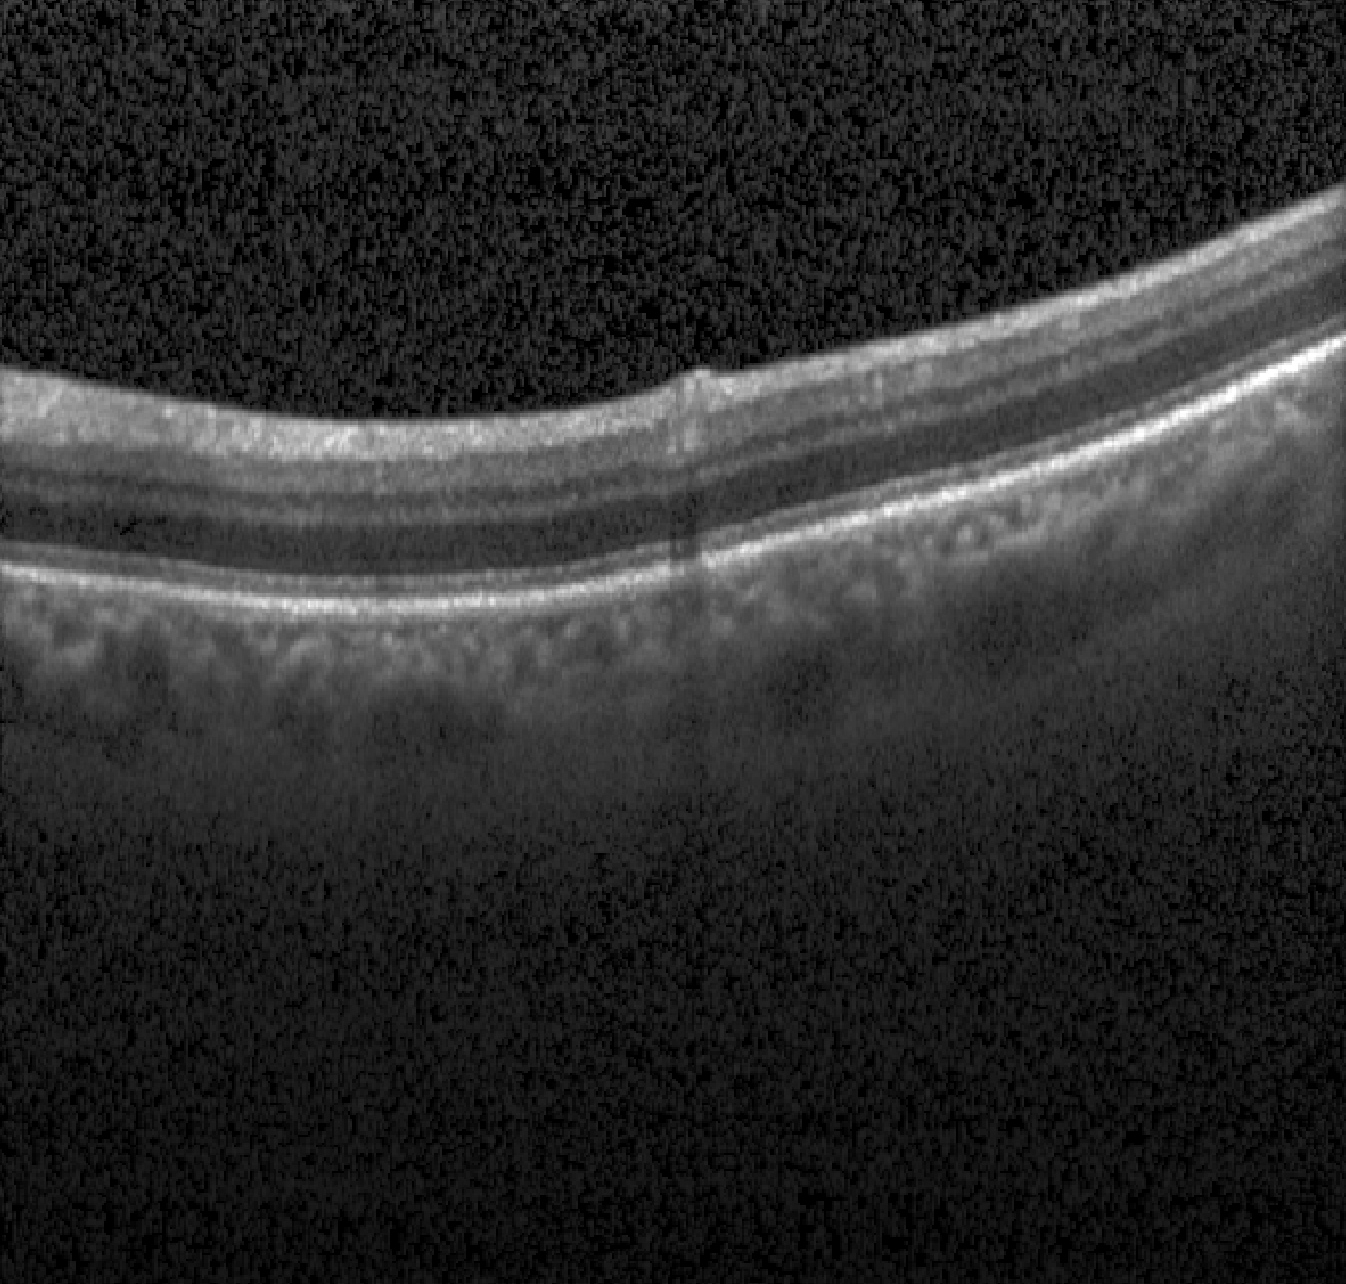

The images used in this study are provided by the MICCAI RETOUCH Group[1]. There were 3 training data sets and a total of 70 volumes, with 24 volumes acquired with each of the two OCT imaging devices: Cirrus (Zeiss) and Spectralis (Heidelberg), and 22 volumes acquired with T-1000 and T-2000 (Topcon, collectively referred to by the manufacturer name in the rest of paper). For each volume from these three devices, the numbers of B-scans were 128, 49 and 128, respectively. Three different types of fluid, namely the intraretinal fluid (IRF), subretinal fluid (SRF) and the pigment epithelial detachment (PED) were manually labeled and provided as ground truth. Although not all B-scans contained fluid, there was at least one type of fluid in each volume. Topcon images with and without macular edema are shown in Fig 1 for each commercial device.

| (a) Cirrus | (b) Spectralis | (c) Topcon |